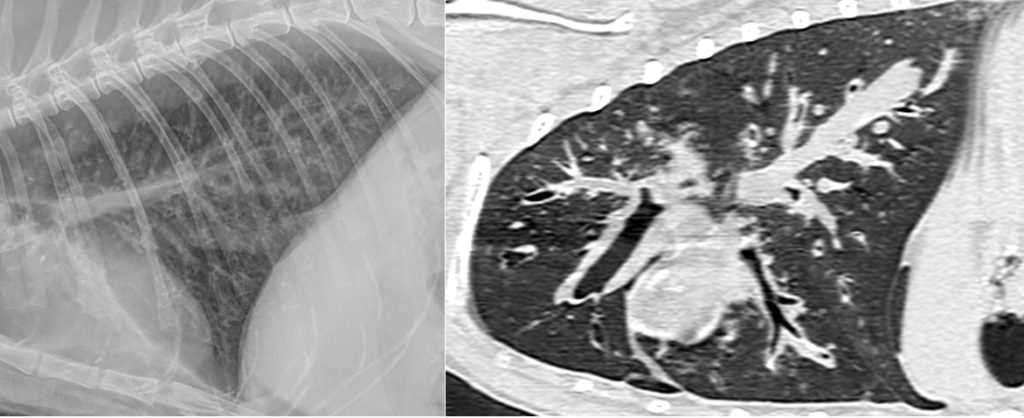

Figure 3 et 4 : opacification bronchique marqué en radiographie à gauche et en tomodensitométrie à droite.